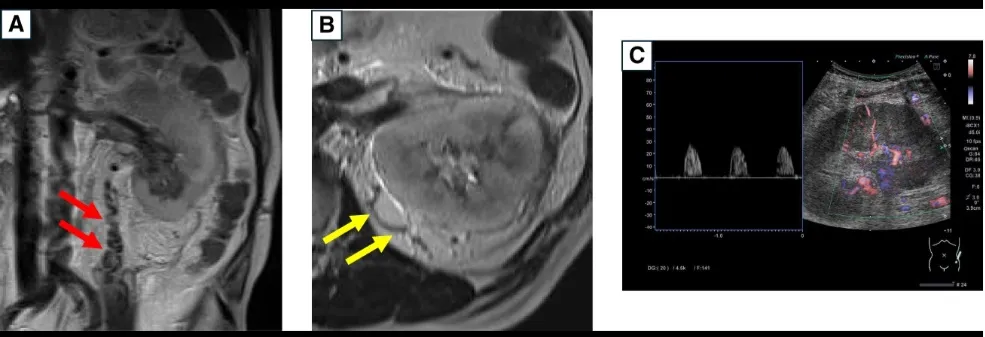

A ressonância magnética (abaixo) mostrou dilatação da veia testicular esquerda e da veia capsular renal. A tomografia computadorizada sem contraste revelou rim esquerdo aumentado, veia renal esquerda dilatada e infiltração perirrenal. Ultrassonografia Doppler mostrou fluxo sistólico isolado nas artérias interlobares, sugerindo congestão renal. Foi confirmado trombose da veia renal com êmbolo na junção com a veia testicular.

Achados de ressonância magnética sem contraste e ultrassonografia Doppler que sugerem trombose da veia renal. (A e B) Ressonância magnética mostrando aumento da (A) veia testicular esquerda e da (B) veia capsular renal. (C) Ultrassonografia Doppler da artéria interlobar mostrando fluxo sanguíneo apenas na fase sistólica.